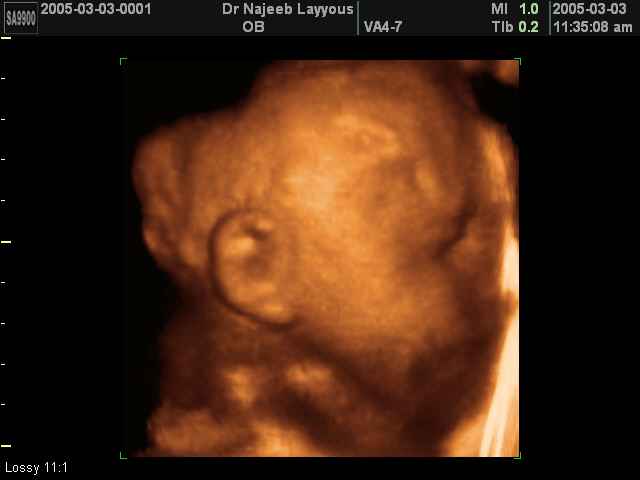

- 3D Photos échographie des parties du fœtus